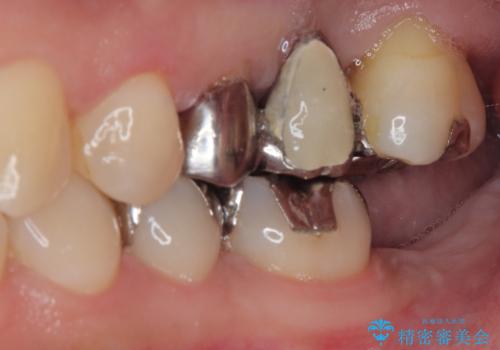

- 奥歯を抜歯してから放置しているとのことで来院された患者様です。

歯が割れて抜歯になってしまったとのことで、咬合力に抵抗できるよう、インプラントによる補綴治療を行うこととしました。